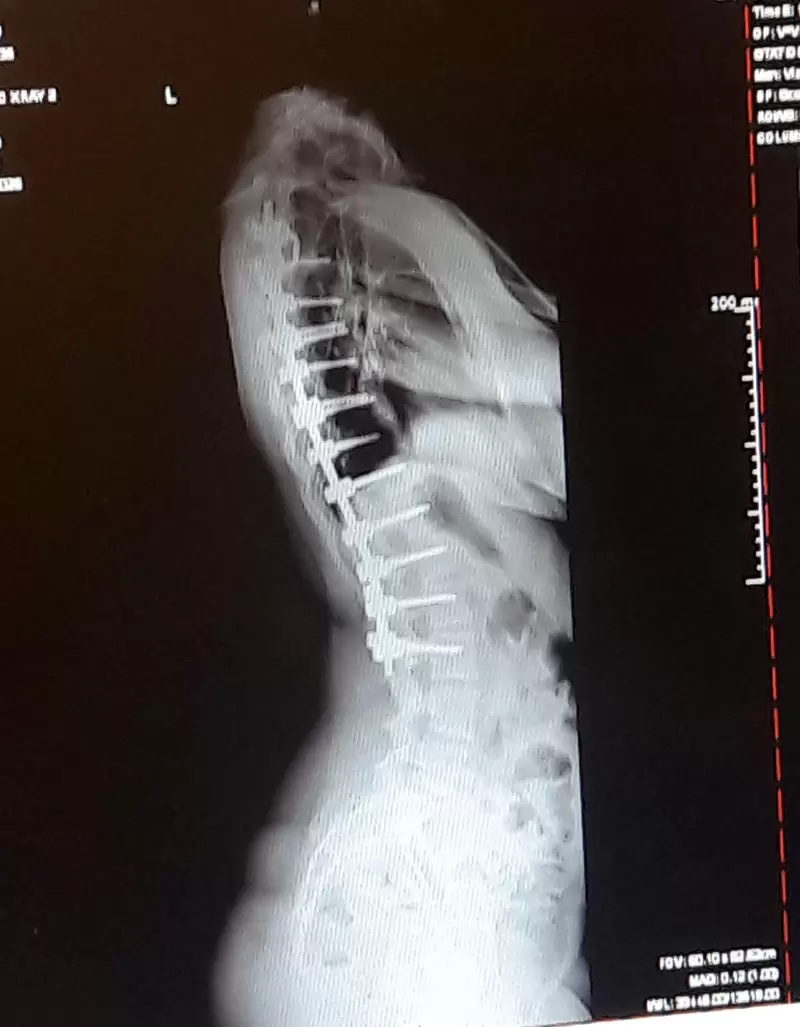

▼脊椎固定骨釘的照片

圖片來自:buzzfeed